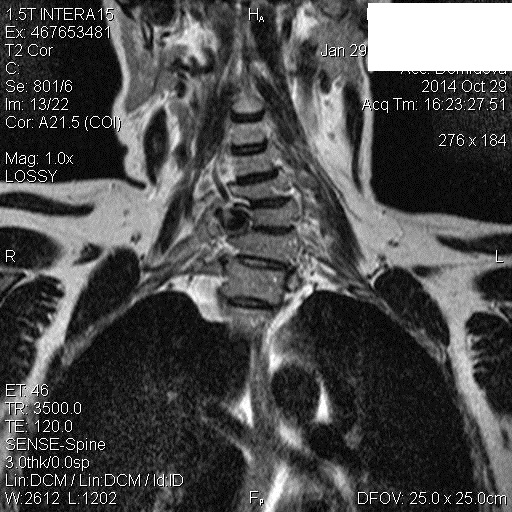

Направительный диагноз-остеохондроз шейного отдела позвоночника. Женщина 1965 года рождения.

Евгений, добрый день.Пациентка по ОМС, назначили только шею . Написала подозрение на аневризму  правой позвоночной артерии , направила по cito к сосудистому хирургу и дообследование сосудов шеи как можно быстрее.